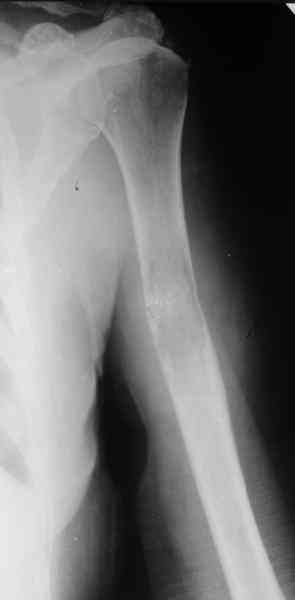

Женщина 53 лет получила патологический перелом правого плеча в феварле, и левого в марте - mts из невыясненного первичного очага.

Онкологи провели облучение, руки на косынки, время от времени наблюдают, вводили зомету.На нас вышли родственники. Состояние пациентки уже не очень, анемия (Hb -50-60 г/л), исхудалв, но асцита нет, в легких чисто. Поскольку женщина совершенно беспомощна, решили сделать остеосиннтез.

Сегодня сделали, Fixion диаметром 7,4 мм. Обе пперации продолжались по 7 мин. Картинки в приложении. Наркоз был диприваном, на спонтанном дыхании. По крайней мере, пока довольны хотя бы анестезиологи, похоже, не верили, что управимся меньше, чем за час ;-)

Гвоздик 7,4 расширяется до 11 мм. Не маловато ли, судя по снимкам?

7,4 мм, рсширяющийся до 11 мм, в принципе, достаточно для плеча. Хотя мне тоже показалось, что можно было бы и потолще. Вообще есть и следующий диаметр, 8,5 мм, расширяющийся до 13,5 мм, но его в наличии на сегодня не было.